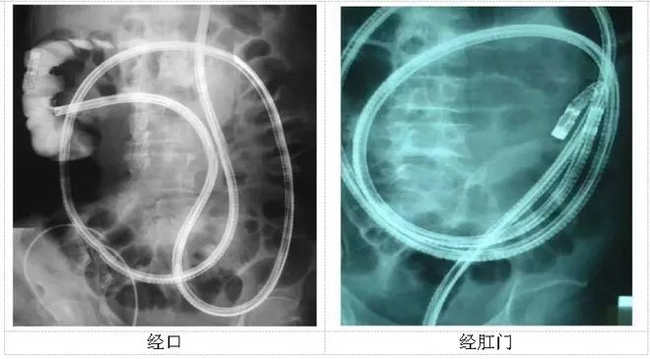

直到小肠镜的出现,为小肠病变肿瘤的检查确诊提供了一个有效的检查方式!

1.不仅可以观察小肠组织和黏膜,而且还有取活检和治疗的双重作用。

近年来,郑州大学五附院消化内镜中心在小肠镜的应用方面取得了较大的进展,拥有一支专业的小肠镜团队以及先进的小肠镜设备,以郑权、于泳、梅璐、黄煌等专家为核心的小肠镜团队在小肠疾病的诊疗方面也积累了丰富的经验。在内镜技术发展中,小肠镜作为一种不可或缺的小肠疾病诊治金标准,在河南省开展的医院仍有限,能够进一步开展小肠镜下微创治疗的单位更是寥寥无几。